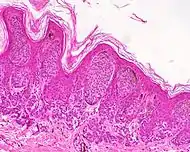

| وحمة داخل الأدمة | داخل الأدمة. | شامة كلاسيكية أو وحمة. وعادة ما يظهر على شكل نتوء مرتفع على شكل قبة على سطح الجلد.[19] | ![]() |

وحمة جلديّة صغيرة، مع أعشاش من خلايا الوحمة (السهام)